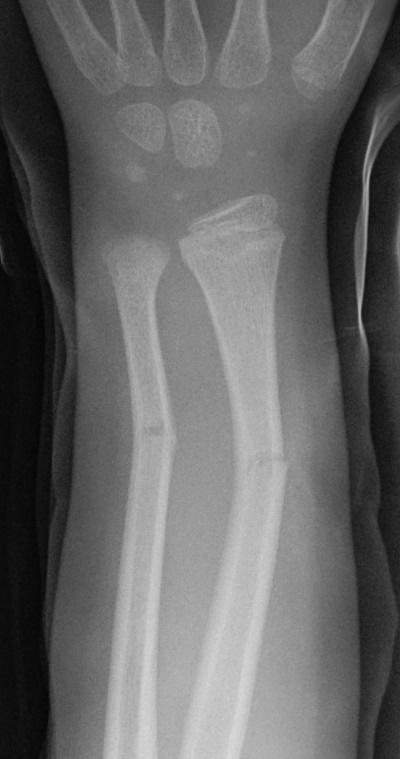

is the correct answer. It is strongly recommended to research the above types of fractures for a better understanding of their x-ray presentation. A green-stick fracture involves an incomplete fracture usually at the shaft of a long bone (as seen here in the radius and ulna). It is caused by a bending-type mechanism of injury. As with all fractures in children, it is important to consider safeguarding issues, especially with mechanisms of injury as such.

Greenstick fracture - e Image used on license from Radiopaedia